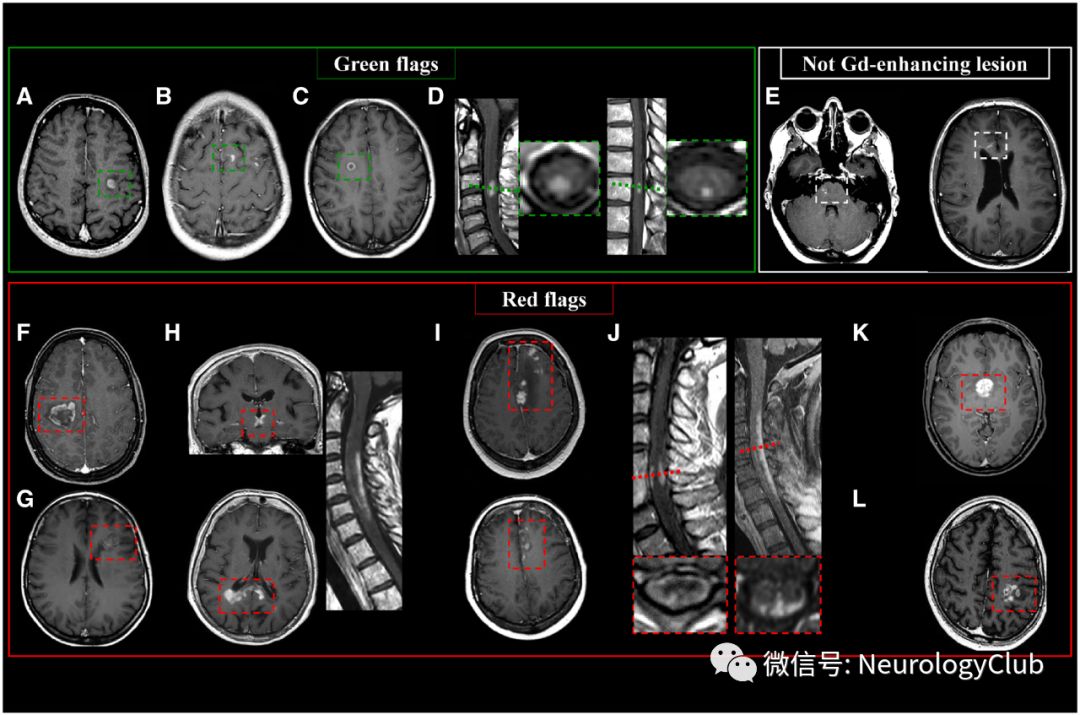

图5:MS患者典型和非典型强化病灶以及不应该计数在内的病灶;左上:绿旗征:MS强化病灶:(A)结节样;(B)开环征;(C)闭环征;(D)脊髓结节样强化;右上:(E)毛细血管扩张症(不纳入诊断标准);底部:红旗征:(F)提示非典型特发性炎性脱髓鞘病灶的不均匀强化瘤样大病灶(>2cm);(G)Balo病带状强化;(H)NMOSD患者间脑、胼胝体云雾状强化和纵向广泛脊髓受累;(I)中枢神经系统血管炎软脑膜、皮质和皮质下不规则强化;(J)神经结节病软脊膜强化及轴位“三叉戟征”;(K)抗Ma2脑炎间脑均匀增强;(L)胶质母细胞瘤不规则不均匀强化